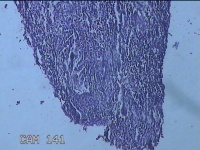

宫腔内容物

性别

女

年龄

47岁

临床诊断

1.异常子宫出血 2.慢性宫颈炎

一般病史

不规则阴道流血21天。

标本名称

大体所见

灰白暗红色不规则碎组织2.5x1.8x0.3cm一堆。

图2